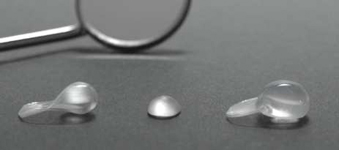

Novinkou v augmentačních metodách, kterou jako první v České republice používáme v našem zařízení je ultrazvuková metoda pomocí polylaktidové membrány - SonicWeld Rx®, kterou zavedl do implantologie v roce 2009 Dr. Dr. G.Iglhaut (Memmingen, Německo).